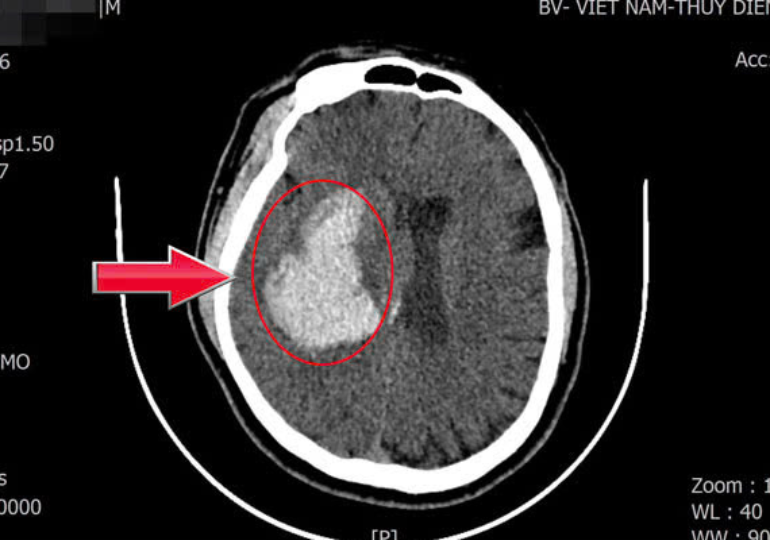

Ngay sau khi tiếp nhận, các bác sĩ đã tiến hành chụp CT sọ não cấp cứu. Kết quả cho thấy bệnh nhân bị xuất huyết não kèm tụ máu trong nhu mô não, gây chèn ép các tổ chức não xung quanh. Trước diễn biến nặng và nguy cơ đe dọa tính mạng của người bệnh, ê-kíp đã nhanh chóng hội chẩn và quyết định phẫu thuật cấp cứu lấy khối máu tụ.